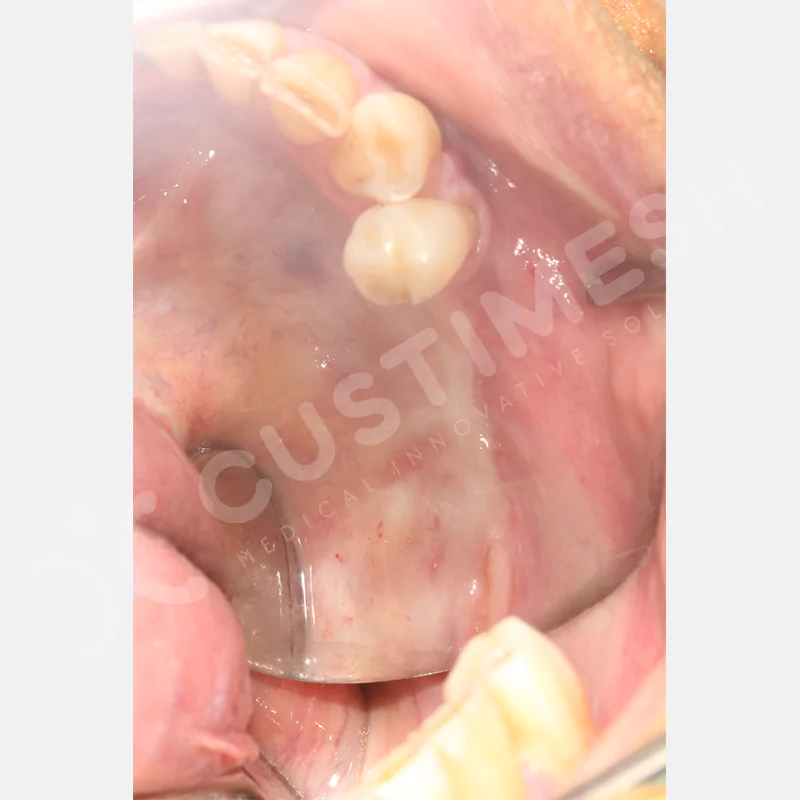

VAKA 1

VAKA 2

VAKA 3